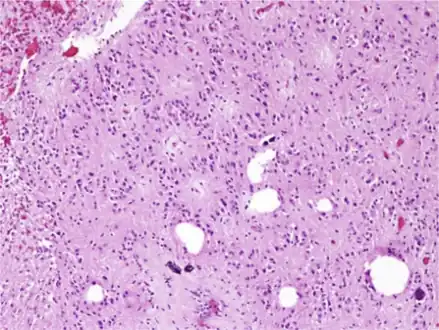

| Micrograph of a subependymoma showing the characteristic clustering of nuclei. H&E stain. | |

Characteristic clusters of nuclei in a dense fibrillary background suggestive of subependymoma -

The diagnosis is based on tissue, e.g. a biopsy. Histologically subependymomas consistent of microcystic spaces and bland appearing cells without appreciable nuclear atypia or mitoses. The nuclei tend to form clusters.